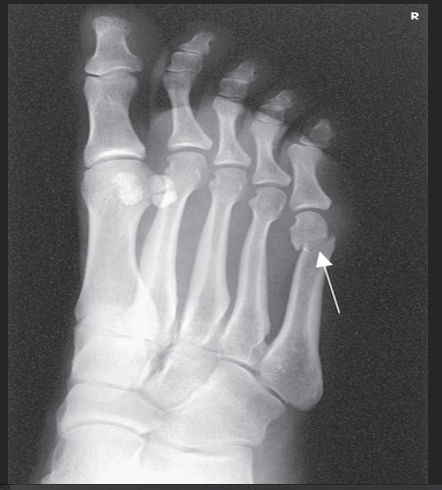

Name this projection.

AP oblique toes

State the degree and type of rotation used.

Medial rotation 30-45 degrees

Which aspect of the foot rests on the IR?

Medial aspect

Where does the CR enter?

Perpendicular to 3rd MTP joint

When radiographing the 1st-2nd toes, which oblique should be used?

Medial (rotate on medial/unaffected side)

When radiographing the 4th-5th toes, which oblique should be used?

Lateral (rotate on lateral/affected side)